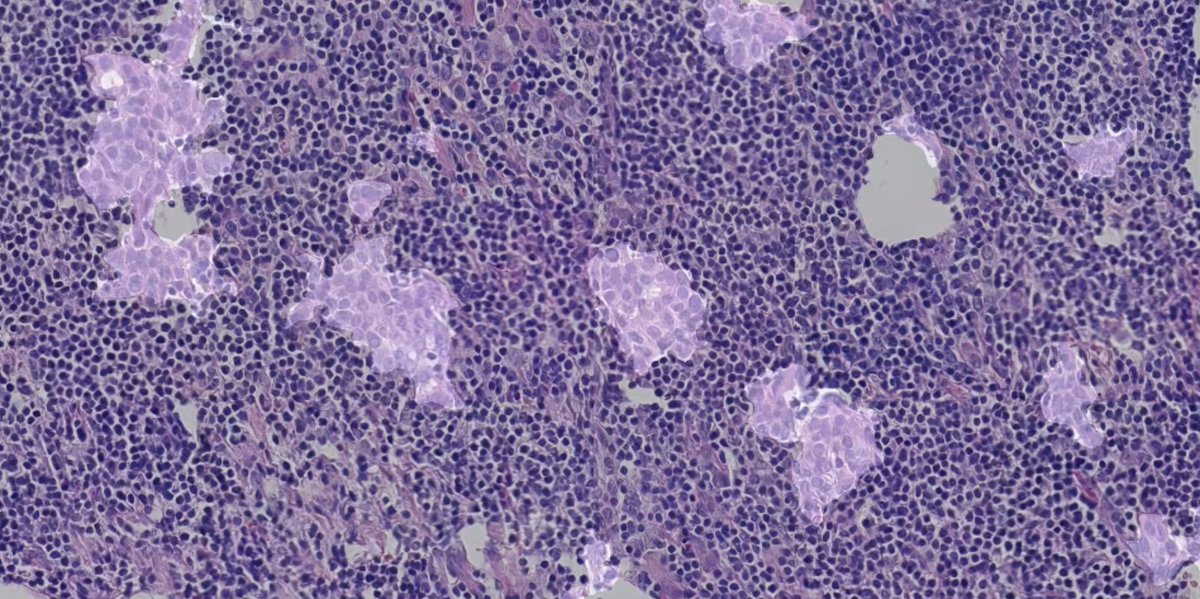

The most comprehensive validation of image search in. histopathology

Just published: Analysis and Validation of #Image #Search Engines in #Histopathology URL: ieeexplore.ieee.org/document/10596… #information #retrieval #search #image #pathology #histopathology #deeplearning #AI #foundationmodels